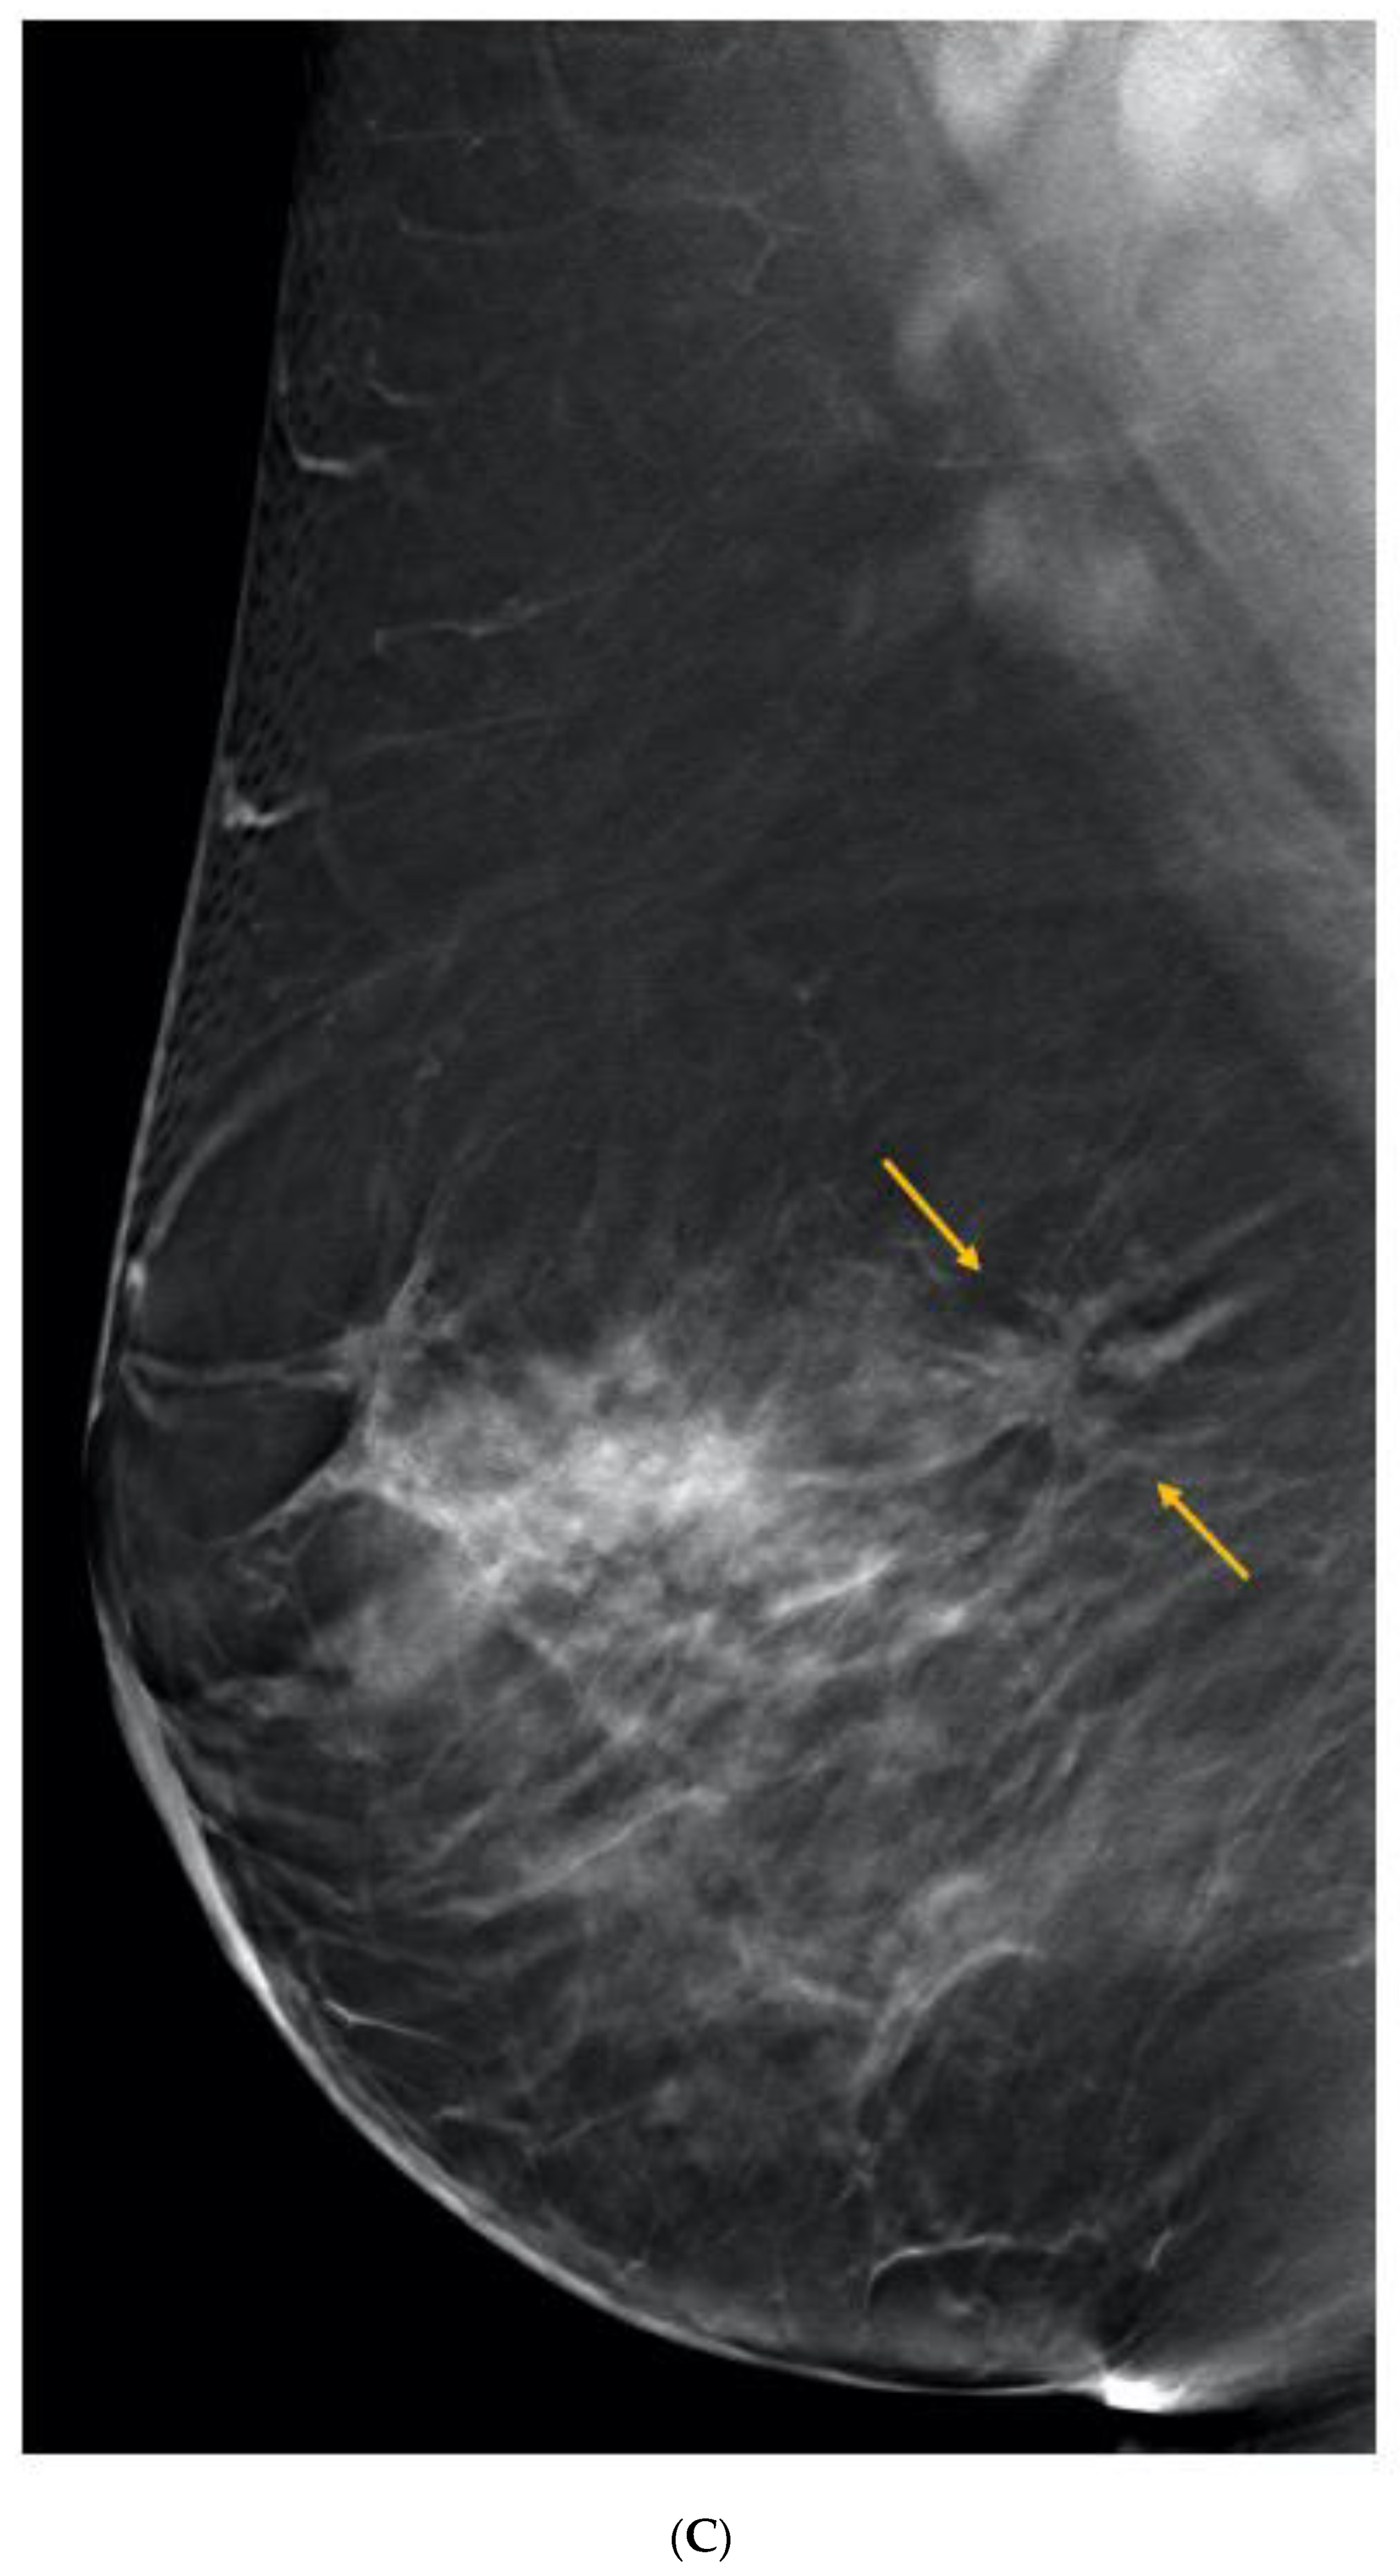

6. Digital Breast Tomosynthesis (DBT)